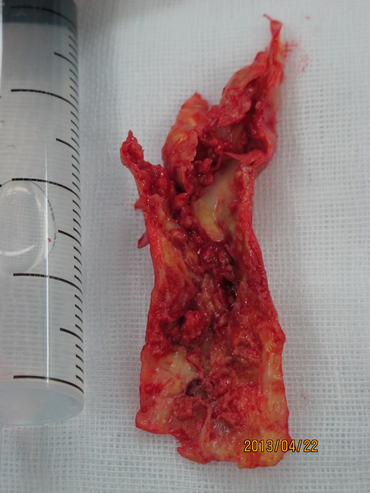

2013年4月22日,张勤奕教授于安贞医院为其施行了左侧颈内动脉内膜剥脱术,术中可见斑块弥漫自颈内动脉至颈总动脉,斑块表面溃疡明显,如豆腐渣样改变。手术圆满成功,患者恢复良好。

下图为手术剥离下的溃疡斑块: